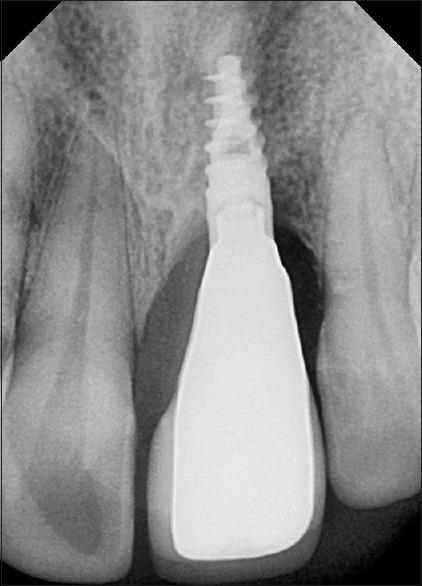

Bone grafting for implant dentistry depends on bone quality, quantity, and biological principles for good outcome. Autogenous bone as donor remains the gold standard among all the available materials. However, it carries unpredictable morbidity and need for different surgical sites. In our report, we describe a simplified approach in bone augmentation for restricted maxillary atrophic defect within the same surgical site as a harvesting site. The method can be an alternative for different intraoral surgical harvesting sites. The patient's left maxillary central incisor before treatment had a large bony defect which was reconstructed though single site approach of augmentation. The implant-supported restoration with healthy periodontium around even after 2 years of review looks promising. The approach can be an alternative for different intraoral surgical sites.

种植牙科的骨移植取决于骨质量、骨量以及实现良好效果的生物学原理。自体骨作为供体在所有可用材料中仍是金标准。然而,它具有不可预测的发病率且需要不同的手术部位。在我们的报告中,我们描述了一种在与采集部位相同的手术部位对上颌局限性萎缩性缺损进行骨增量的简化方法。该方法可作为不同口腔内手术采集部位的替代方法。治疗前患者的左上中切牙有一个大的骨缺损,通过单部位增量方法进行了重建。即使在复查2年后,周围有健康牙周组织的种植体支持修复看起来前景良好。该方法可作为不同口腔内手术部位的替代方法。